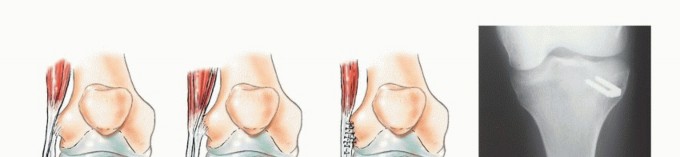

أنواع الاستئصال الجراحي للشظية القريبة

هناك ثلاثة أنواع رئيسية من استئصال الأورام حول الشظية القريبة:

-

الكشط (Curettage):

- الإشارة: يُستخدم للأورام الحميدة العدوانية والأورام الغرنية منخفضة الدرجة المرتبطة بتدمير قشري بسيط وامتداد خارج العظم ضئيل.

- الإجراء: يتم إزالة الورم يدويًا بواسطة مكشطة، ثم تُستخدم مثقاب عالي السرعة لتنظيف جدران تجويف الورم بدقة لضمان إزالة أي مرض مجهري متبقي.

- الحفاظ: يتم الحفاظ على العصب الشظوي المشترك والأوعية الدموية.

-

الاستئصال من النوع الأول (Type I Resection):

- الإشارة: يُستخدم لعلاج الأورام الحميدة العدوانية والأورام الغرنية منخفضة الدرجة التي تسببت في تدمير قشري كبير للشظية القريبة.

- الإجراء: يشمل إزالة الشظية القريبة، وغلاف عضلي رقيق من جميع الأبعاد، وموقع ارتباط الرباط الجانبي الوحشي (LCL). يتم الحفاظ على العصب الشظوي المشترك وفروعه الحركية، ويتم استئصال المفصل الظنبوبي الشظوي داخل المفصل.

- الحفاظ: يتم الحفاظ على العصب الشظوي والشريان الظنبوبي الأمامي عادةً.

-

الاستئصال من النوع الثاني (Type II Resection):

- الإشارة: يُستخدم لعلاج الأورام الغرنية عالية الدرجة، والتي عادةً ما يكون لديها تدمير قشري كبير مع امتداد خارج العظم.

- الإجراء: يشمل إزالة الشظية القريبة والمفصل الظنبوبي الشظوي، والحجرات العضلية الأمامية والجانبية، والعصب الشظوي، والشريان الظنبوبي الأمامي بشكل كامل. يتطلب هذا النوع ربط الشريان الظنبوبي الأمامي وقد يتطلب أيضًا التضحية بالشريان الشظوي.

- الحفاظ: لا يتم الحفاظ على العصب الشظوي والشريان الظنبوبي الأمامي.

يوضح الجدول التالي الهياكل التشريحية التي يتم إزالتها مع أنواع الاستئصال المختلفة للشظية القريبة:

| نوع الجراحة | موقع ارتباط الرباط الجانبي الوحشي | الشريان الظنبوبي الأمامي | العصب الشظوي |

|---|---|---|---|

| الكشط | سليم | سليم | سليم |

| استئصال من النوع الأول | مُزال | سليم | سليم |

| استئصال من النوع الثاني | مُزال | مُزال | مُزال |